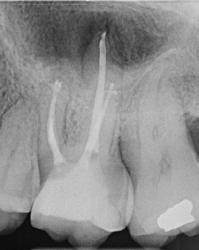

Gyökéramputációt főként a furkáció érintett nagyőrlő fogak ellátása során szoktunk alkalmazni. Derks és mtsai. vizsgálatában a gyökéramputált nagyőrlő fogak közel 80%-a 20 évvel a beavatkozás elvégzését követően is megtartott volt. 1998 októberében egy 39 éves férfi páciens a jobb alsó kvadránsban jelentkező ínyérzékenység miatt kereste fel rendelőnket. A klinikai vizsgálat során jobb alsó első és második nagyőrlő fog között (46–47) nagy kiterjedésű csontveszteséget észleltünk. Ettől eltekintve a teljes fogazat parodontális státusza megfelelőnek bizonyult. A jobb alsó kvadránsban végzett szenzibilitás vizsgálat során arra az eredménye jutottunk, hogy a 46-os fog vélelmezhetően elhalt (10. ábra).

A páciens beleegyezését követően a 46-os fog disztális gyökere, a disztális gyökér felett lévő koronális rész megőrzése mellett rezekcióra került (11. ábra). A rezekciót követően a referáló orvos a 46. és 47. fogak koronáját Ribbond szalag és kompozit segítségével egymáshoz rögzítette. A sebészi beavatkozást követően 22 évvel készült kontrollfelvételen a lézió csontos telődése, kortikális csontállomány kialakulása, valamint a furkáció körüli csontos regeneráció volt megfigyelhető (12. ábra) A károsodott fogak megtartására szolgáló lehetőségek fejlődésének, valamint az implantátumok behelyezésével kapcsolatos rizikófaktorok jobb megértésének köszönhetően ma már más szemmel vizsgáljuk a fogak eltávolításának szükségességét. A kérdéses prognózissal vagy a kis protetikai értékkel rendelkező fogak eltávolítása előtt mindig érdemes felmérni az ezzel elérhető lehetséges előnyök nagyságát. A kemény- és lágyszöveti pótlás lehetőségeinek fejlődésével, a PRF elérhetőségével, a minimálinvazív sebészeti módszerek és az operációs mikroszkópok elterjedésével, valamint a varróanyagok és varrat technikák egyre kifinomultabbá válásával ma már alaposan el kell gondolkodnunk az előtt, hogy egy fogat egy implantátum behelyezése érdekében eltávolítsunk. Mára sokkal kedvezőbb prognózist és sokkal nagyobb sikerességet tudunk elérni a korábban menthetetlennek gondolt fogak kezelése során.